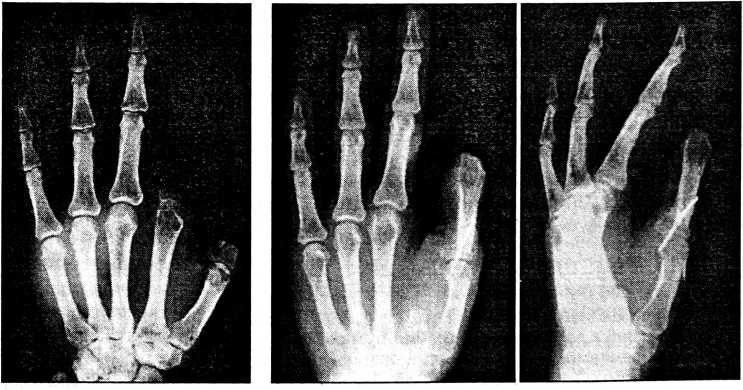

Больная Г., 33 лет, поступила в клинику 2.11.92 с диагнозом: культи I, II пальцев левой кисти на уровне оснований основных фаланг. Травму получила на работе 4.08.92 в результате попадания левой кисти под пресс. При поступлении отмечаются дефекты I, II пальцев (рис. 2), практически полное отсутствие двустороннего схвата кисти, в связи с чем больная не может работать по своей специальности.

С целью восстановления I пальца и функции двустороннего схвата кисти выполнено двухэтапное перемещение культи II пальца с фрагментом пястной кости на культю I пальца. Во время операции первая тыльная межкостная мышца отсечена от места прикрепления, а после перемещения сегмента уложена на дно образовавшегося межпальцевого промежутка и подшита к III пястной кости. Образовавшийся в первом межпальцевом промежутке дефект кожи размером 4x6 см замещен кожно-фасциальным лоскутом соответствующего размера, взятым с тыльной поверхности левой стопы. Послеоперационное течение без осложнений. Перемещенный сегмент и пересаженный лоскут полностью прижили.

Пациентка осмотрена 30.03.98. Наступила полная консолидация костных фрагментов (см. рис. 2).

Рис. 2. Внешний вид и рентгенограммы кисти больной Г. до и через 6 лет после операции.

Восстановлен двусторонний схват кисти. Пересаженный лоскут эластичный, подвижный, не ограничивает движений I пальца. Профессиональная трудоспособность восстановлена.